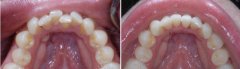

孩子前牙拥挤有危害吗?

前牙拥挤在牙颌畸形中是较为常见的。前牙拥挤的原因主要是颌骨前部发育不足...【详细】

牙齿拥挤要怎么修复?

牙齿拥挤是常见的错合畸形,表现为牙齿拥挤错位排列不齐;而拥挤牙齿的龋及...【详细】

矫正牙齿拥挤需要拔牙吗?

牙齿拥挤是患者内心的一块石头,严重影响外观,还会影响身体健康,很多人因...【详细】